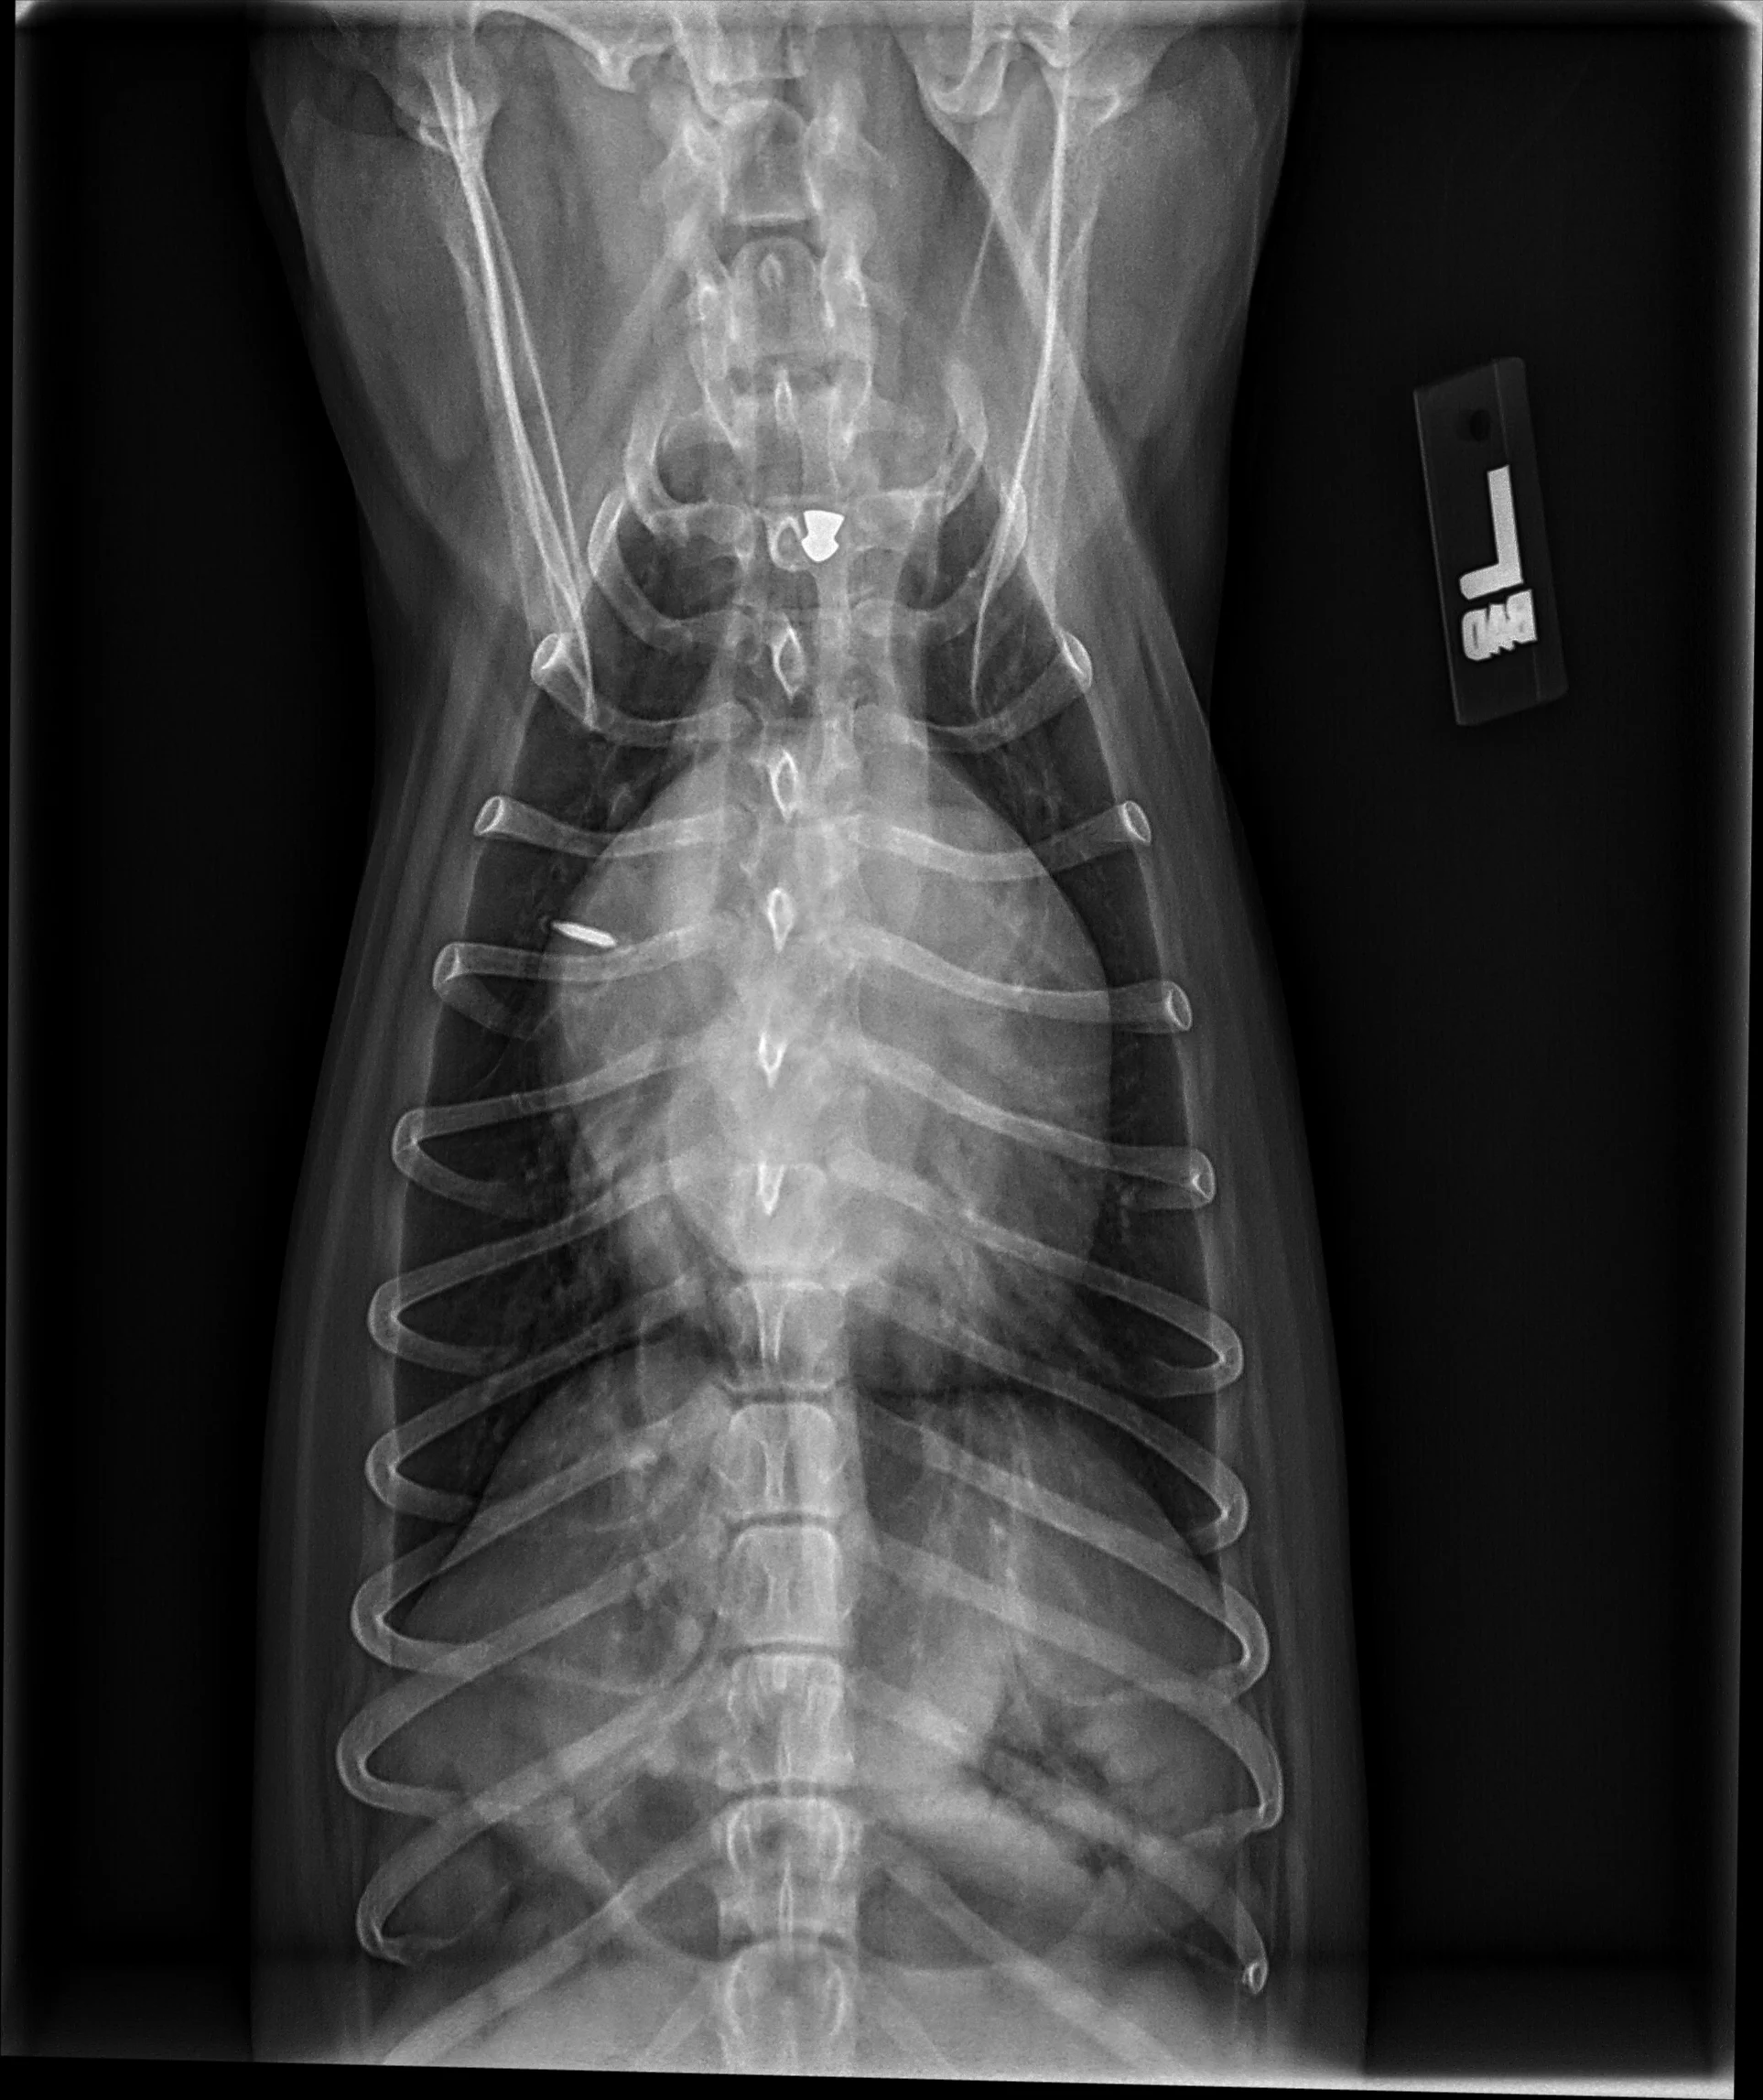

FIGURE 11 Right lateral (left) and VD (right) projections of a crossbreed dog with tricuspid valve dysplasia. The cardiac silhouette has increased width, and the regions of the right atrium and ventricle show roundness. The cardiac apex is displaced to the left secondary to right-sided enlargement (right). The caudal vena cava (arrowheads) is dilated, and there is loss of abdominal serosal detail secondary to increased systemic venous pressures and right-sided CHF, respectively. The pulmonary vasculature is small secondary to pulmonary hypoperfusion (given significant regurgitation across the tricuspid valve and decreased forward blood flow). VHS, VLAS, M-VLAS, and VRHi collected from the right lateral view are 12.3, 2.3, 2.7, and 3.8, respectively. Images courtesy of Bruna Del Nero, DACVIM (Cardiology)